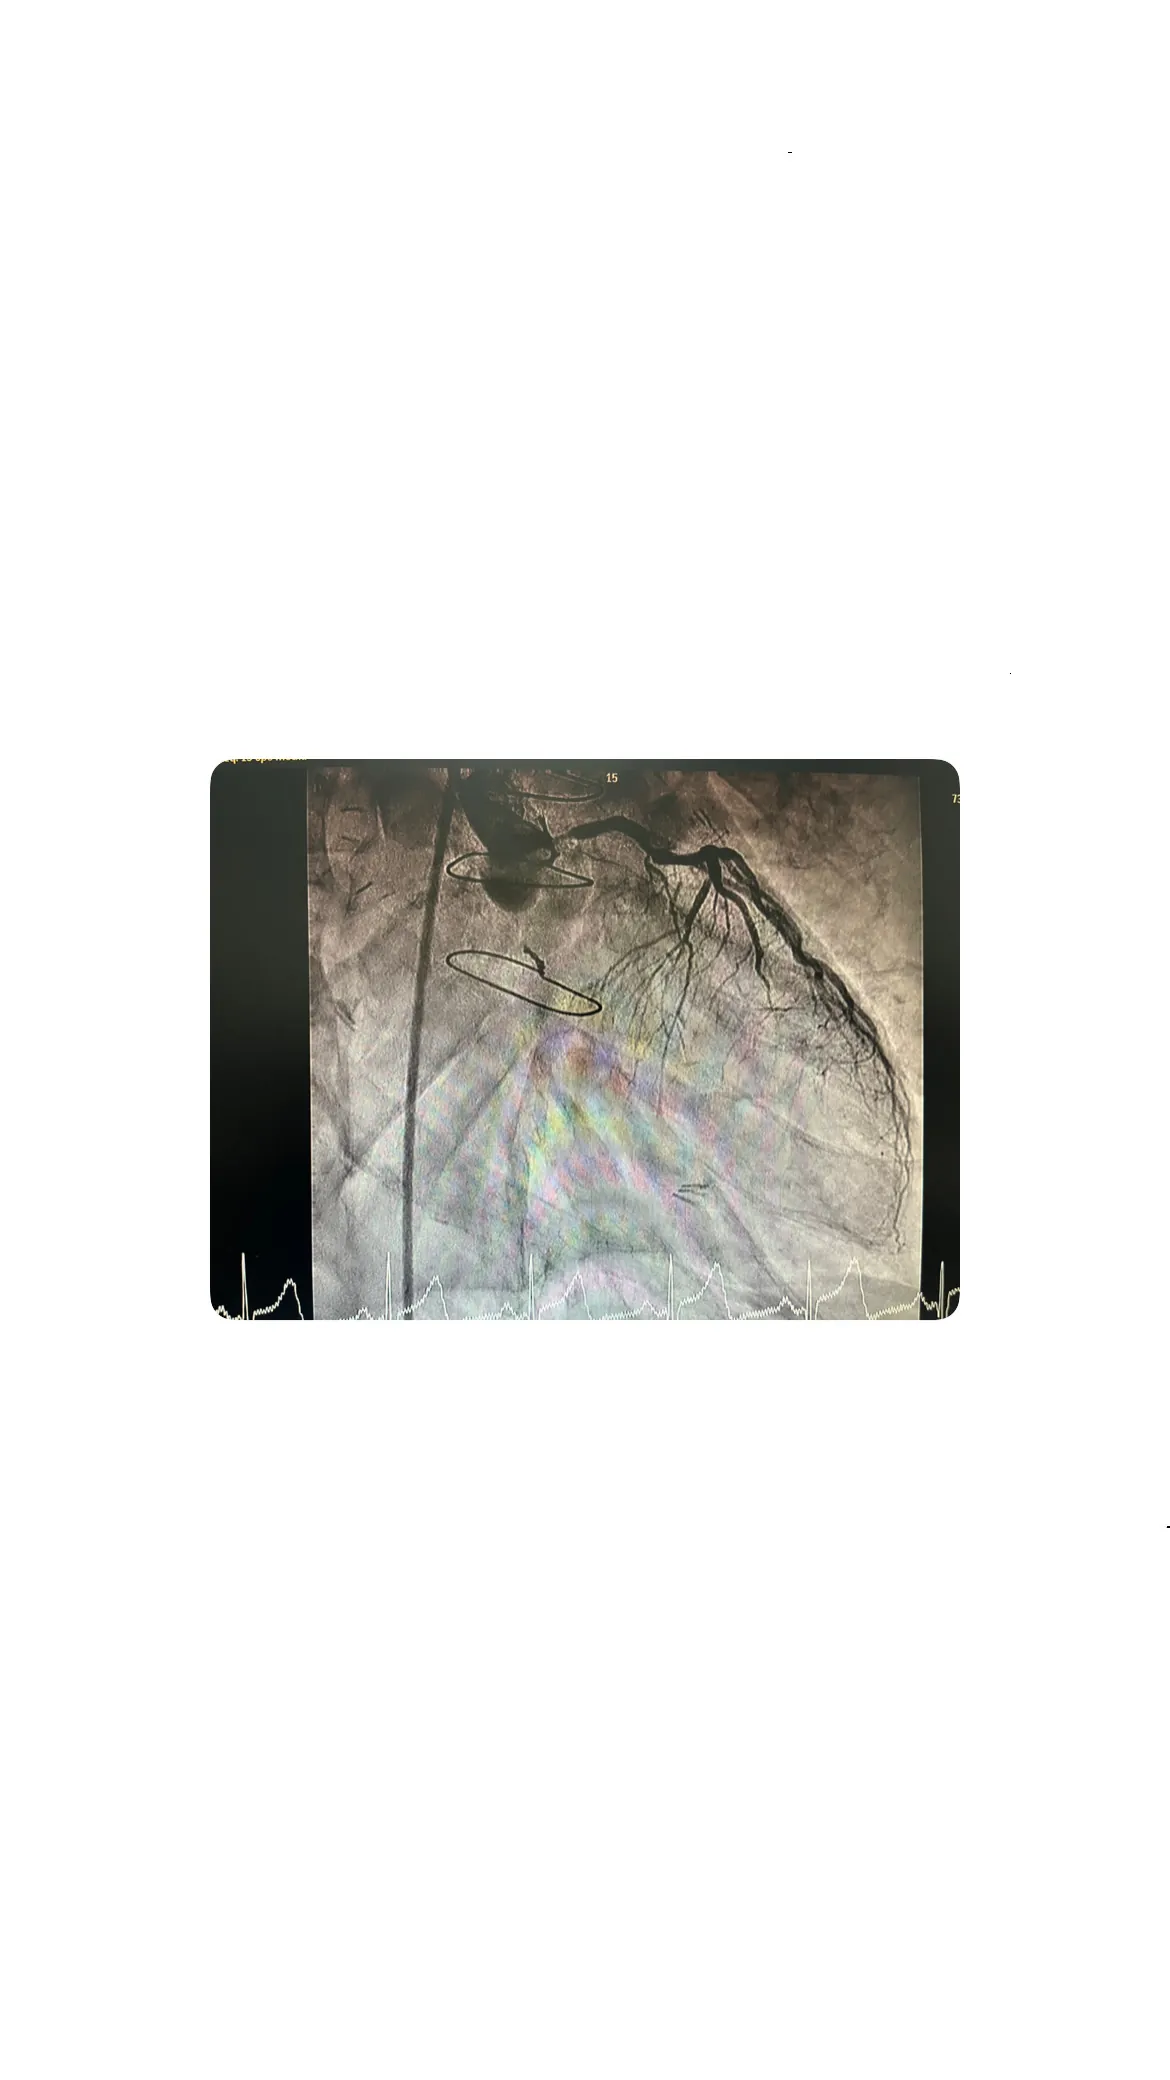

Subida del catéter y visualización del árbol coronario

Una vez que se logró el acceso a través de la arteria femoral, el catéter fue guiado hacia el corazón. Este procedimiento permitió la visualización del árbol coronario, proporcionando una imagen clara de las arterias y los bypasses. La visualización es crucial para identificar cualquier obstrucción o problema en el flujo sanguíneo que pudiera estar causando el dolor torácico del paciente.

Hallazgos en el árbol coronario izquierdo y el tronco común

Lesión crítica en el tronco común

Durante la evaluación del árbol coronario izquierdo, se identificó una lesión crítica en el tronco común. Este hallazgo es significativo, ya que el tronco común es una arteria principal que suministra sangre a gran parte del corazón. Sin embargo, a pesar de la gravedad de la lesión, los bypasses estaban funcionando adecuadamente, proporcionando un flujo sanguíneo suficiente para compensar la obstrucción.

Relevancia de la permeabilidad de los bypasses

Imágenes angiográficas: grapas, suturas y complejidad del bypass

Visualización de las grapas y la sutura de esternotomía

Las imágenes angiográficas obtenidas durante el cateterismo revelaron detalles interesantes sobre la cirugía de bypass previa. Se pudieron observar claramente las grapas utilizadas en los bypasses y la sutura de la esternotomía. Estos elementos son testimonio de la complejidad y precisión requeridas en este tipo de procedimientos quirúrgicos.

Complejidad anatómica de los bypasses coronarios

La anatomía de los bypasses coronarios es intrínsecamente compleja. Cada bypass debe ser cuidadosamente colocado para asegurar un flujo sanguíneo adecuado y evitar complicaciones. En este caso, la complejidad anatómica fue evidente en las imágenes, destacando la habilidad y precisión del equipo quirúrgico que realizó la cirugía.